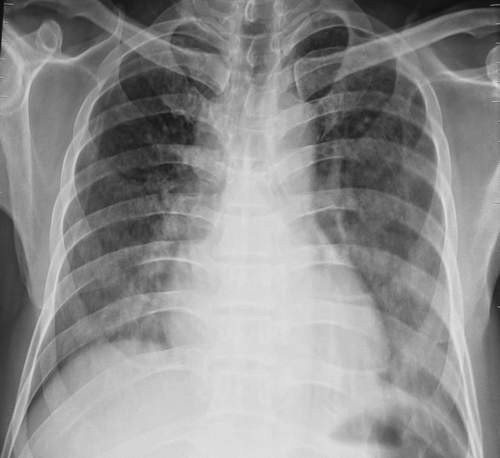

Bệnh diễn biến phức tạp với tổn thương nhiều cơ quan như viêm não, viêm phổi, nấm máu và suy thận. Đã điều trị tích cực bằng kháng sinh, nuôi dưỡng, thông khí nhân tạo, lọc thận, bù dịch điện giải... nhưng người bệnh bị suy hô hấp nặng và đã tử vong sau hơn 3 tháng mắc bệnh.

Trên bệnh nhân diễn biến lâm sàng ban đầu là hội chứng nhiễm khuẩn nhẹ, sau đó xuất hiện các triệu chứng về hô hấp, suy thận và viêm não; xét nghiệm cùng thời điểm thấy tổn thương ở phổi, suy thận, thay đổi dịch não tủy, nhiễm nấm máu và nấm trong dịch não tủy. Như vậy, bệnh nhân đã bị nhiễm nấm máu, từ đó nấm lan rộng khắp cơ thể và xâm nhập vào hệ thần kinh trung ương.

| Hình ảnh nấm phổi. |